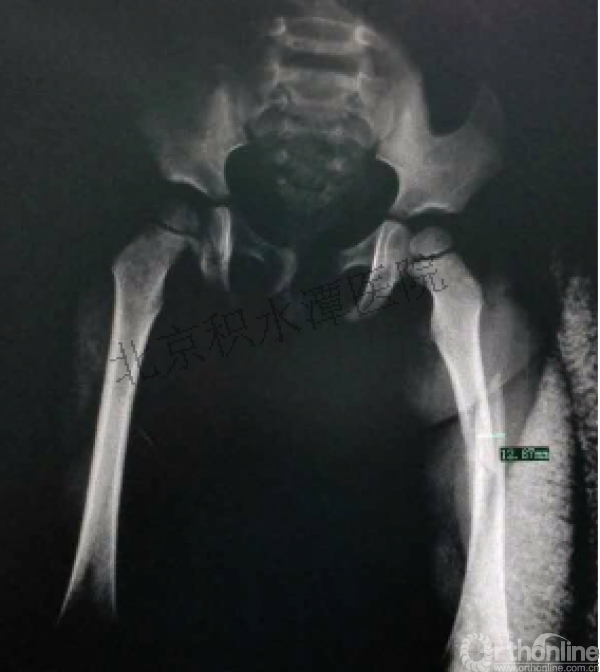

病例分享二

2岁、股骨干骨折,切开+内固定

简单牵引即可!为什么要如此大动干戈?

现实中又是怎样的呢?不知道这属于知识缺乏范畴还是道德品质问题?

匪夷所思!

新生儿股骨干骨折

为什么要手术治疗?

医源性损伤—不愈合!

不具备对儿童骨骼特点的基本了解,不了解儿童骨折的特点,想当然地治疗!